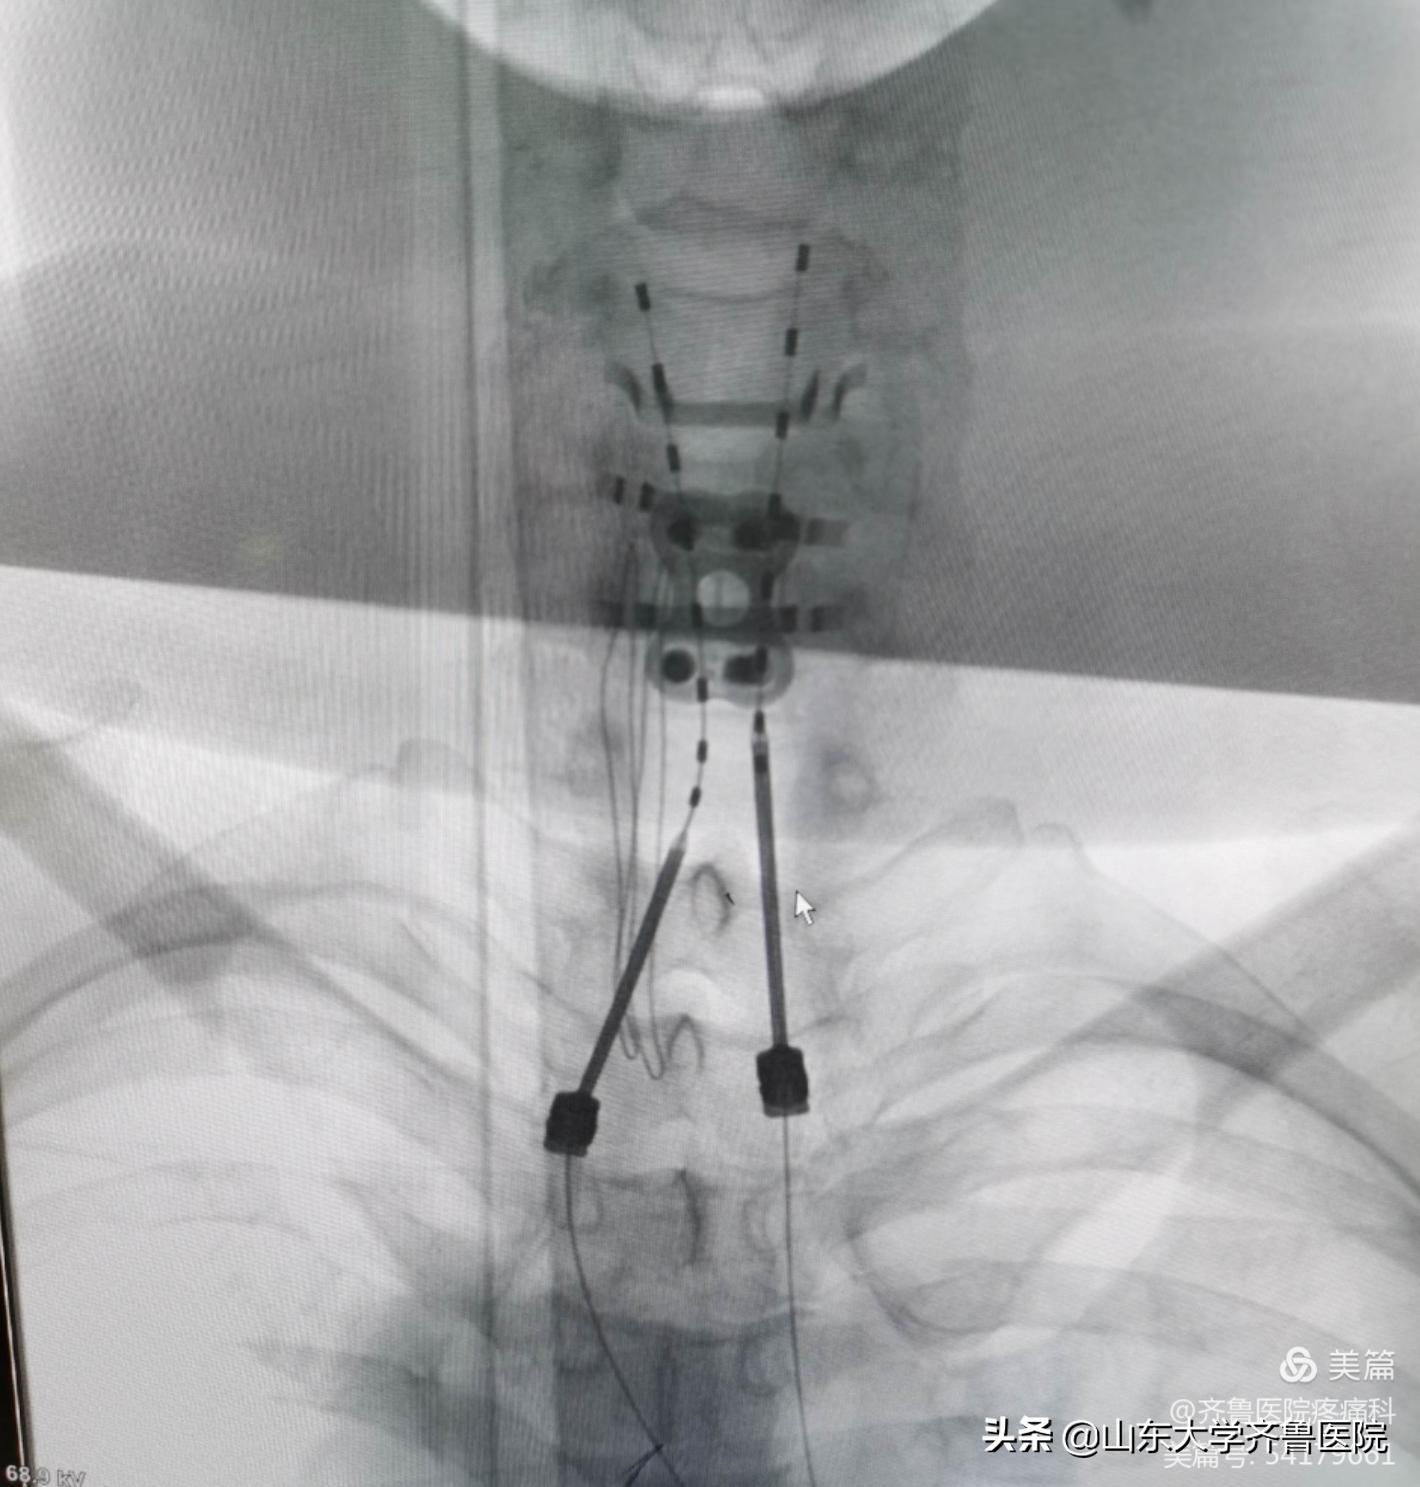

图1.带状疱疹性神经痛患者术后X线检查电极位置良好

病例2 患者中年男性,46岁,因“四肢及颈胸背部疼痛2年11个月”以“颈髓损伤后顽固性疼痛;截瘫”收入院。入院VAS评分9-10分。患者应用“普瑞巴林、氨酚羟考酮、曲马多、哌替啶”等止痛药物效果差。术前评估后,患者在局麻下行脊髓电刺激器植入术,植入双侧针状电极及临时刺激器。术中开机程控,患者感疼痛减轻,VAS评分2分,术后未再应用针剂镇痛,口服药物减量,经程控调整,VAS评分稳定至1-3分。4天后行永久脊髓电刺激器植入术,患者VAS评分稳定于1-2分,未出现术后不良反应及并发症。

图2.颈髓损伤后顽固性疼痛患者术中穿刺植入针状电极

图3.电极测试良好